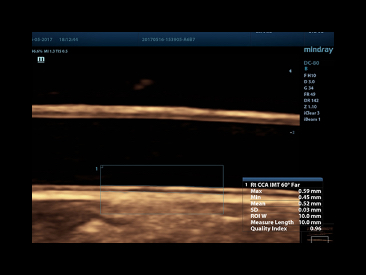

The best patient care is your ultimate goal. To achieve this requires confident diagnosis even with daily increases in patient throughput. Built on the foundation of MindrayвАЩs continuous customer insights into clinical needs and the inheritance from premium technology, the DC-80 with X-Insight is designed to help you manage your daily output with high efficiency, no matter what type patients and clinical challenges you will face.

eXceptional intelligence

Intelligence throughout entire workflow